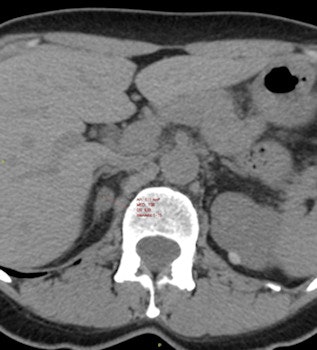

The study, which took place between January 1995 and September 2010 at the S. Orsola-Malpighi Hospital in Bologna, revealed that some tumors become more active over time and that the risk of CV event rises in adrenal incidentaloma patients with mild hypercortisolism, even when the clinical signs of overt hypercortisolism are not present.

The study cohort was composed of 198 consecutive outpatients who were assessed every 18 to 30 months over the first five years before being divided into one of three groups: those with stable mild hyperproduction of cortisol (in which 16.7% of patients experienced a CV event); those with mild hyperproduction of cortisol which worsened over the five-year period (in which 28.4% of patients experienced a CV event); and those with nonfunctioning tumors (in which 6.7% experienced a CV event). Individual follow-up ranged from 26 months to 15 years.

Compared with stable nonsecreting adrenal incidentaloma patients, unadjusted survival for CV-specific mortality was lower in patients with stable mild hypercortisolism (97.5% versus 78.4%) and those with worsened secreting patterns (97.5% versus 60%). Furthermore, survival rates for all-cause mortality were lower in patients with stable mild hyperproduction of cortisol (57%) compared with those with stable nonsecreting tumors (91.2%).